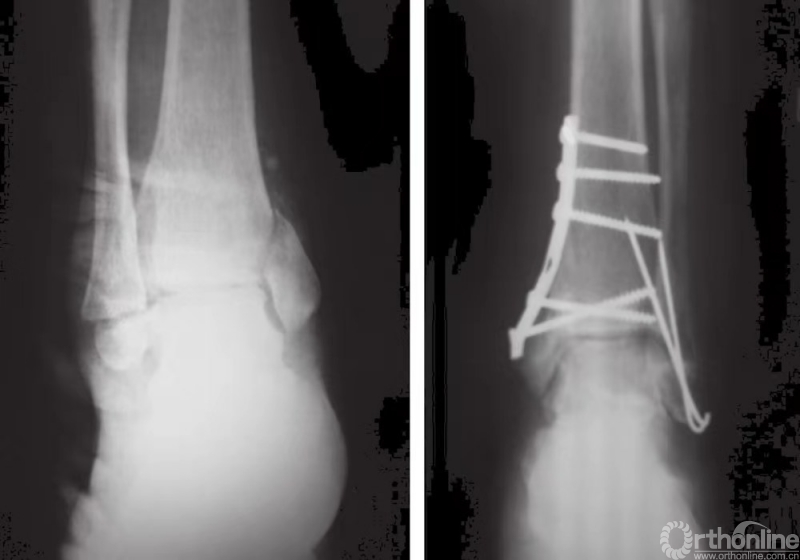

实用经验|这才是踝关节骨折的最佳方案

在下肢骨折中,踝关节骨折最为常见。在过去的50年中,踝关节骨折的发病率日渐升高。近来,随着老年人群体发病率的增长,固定的牢固性问题变得更加复杂,新的固定技术有待研发。

由于机制不同,踝关节骨折可能涉及内踝骨折、外踝骨折或后踝骨折。保守治疗不适用于有移位的双踝骨折,但适用于无移位的内踝和外踝骨折。如果是单纯性内踝骨折,在常规放射性检查中,应查看是否伴有腓骨高位骨折,以防遗漏。如果是单纯性外踝骨折,也应注意查看是否有迹象表明伴有内侧损伤,特别是三角韧带损伤。

踝关节骨折一般有两种分类方法。Davis-Weber分类法根据腓骨骨折线的位置,将踝关节骨折分为A、B、C三型:A型中的骨折线在下胫腓联合以下,B型中的骨折线经下胫腓联合,而C型中的骨折线在下胫腓联合之上。Lauge-Hansen分类法的根据则是足在受伤时的位置以及暴力下距骨旋转的方向(表1)。

在踝关节骨折中,旋后外旋型损伤是最为常见的骨折类型。下胫腓联合损伤通常与旋转所致损伤相关。